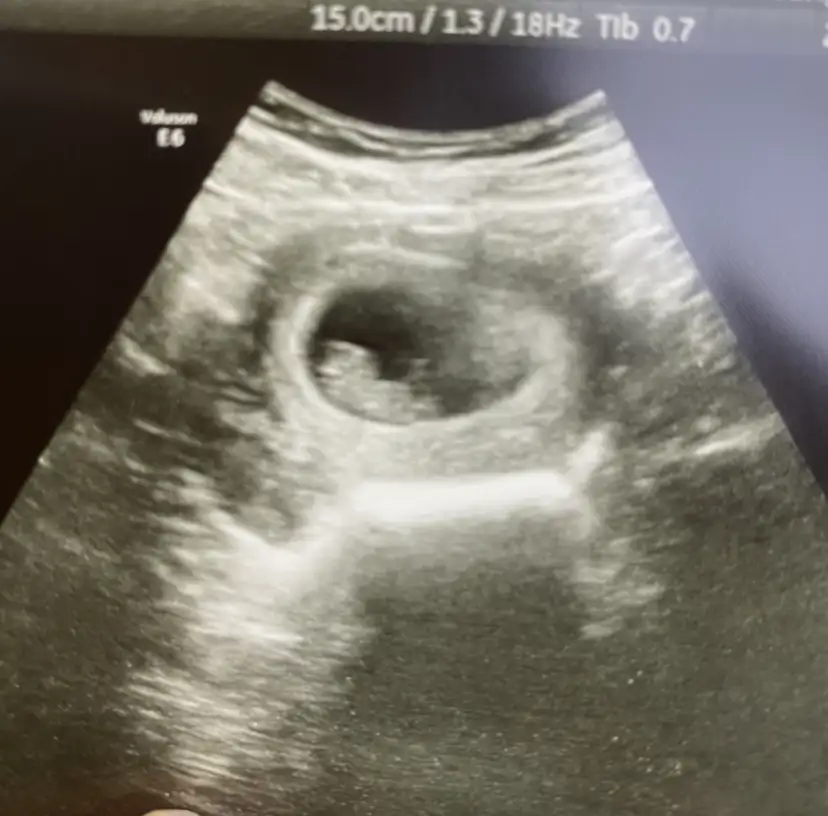

Merhaba ☺️ 12+3 ultrasonumuz bizim için de yorum yapabilir misiniz?

Bizim dünkü kontrolümüzden, karından 8+4. İki foto ekliyorum tahminde bulunabilir misin Pasha22 Pasha22

merhaba Pasha22 Pasha22 :KK200: 9+3 kontrolümüzden, cinsiyet tahmini yapabilir misin:)

9+3 karından bakabilir misiniz?

Merhaba rica etsem benimkinede bakarmisin. Karindan ultrason.6+4 . Bugunde vajinadan bakildi solda ve fasulye seklindeydi kese ama kagit verilmedi.